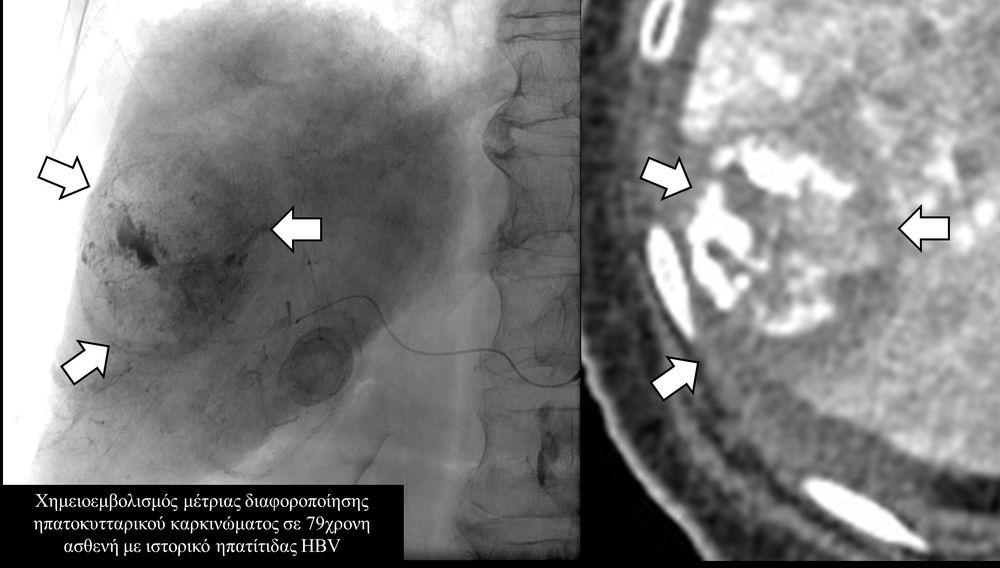

Ο χημειοεμβολισμός είναι μέθοδος τοπικής χημειοθεραπείας για πρωτοπαθή και δευτεροπαθή νεοπλάσματα του ήπατος. Σκοπός του είναι η τοπική έγχυση χημειοθεραπευτικού σε κλάδους της ηπατικής αρτηρίας, ώστε να επιτευχθούν υψηλές συγκεντρώσεις τοπικά στην ηπατική εξεργασία χωρίς να προκαλούνται οι συστηματικές επιπλοκές τοξικότητας του χημειοθεραπευτικού. Επιπλέον προκαλείται τοπική ισχαιμία στην περιοχή του όγκου από τα εμβολικά υλικά-μικροσφαιρίδια εμβολισμού.

Ο χημειοεμβολισμός έχει καθιερωθεί σαν θεραπεία εκλογής στο ενδιάμεσο στάδιο του ηπατοκυτταρικού καρκινώματος.